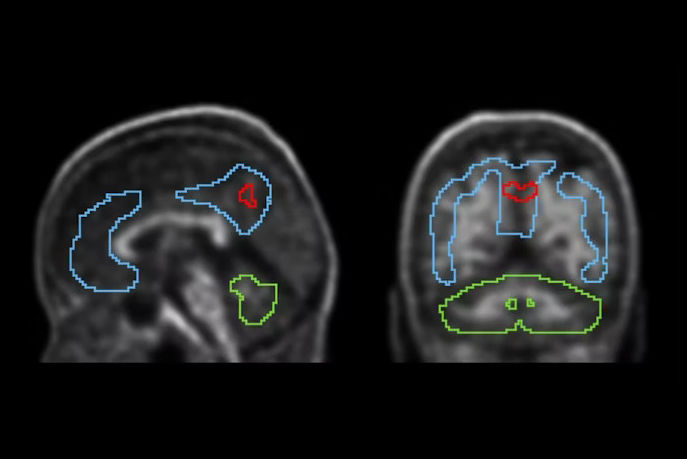

To address the knowledge gap, the group explored whether there is a longitudinal relationship between depressive symptoms and increased neurofibrillary tau tangles in the brain, a hallmark of the disease.

The researchers gathered data from 300 patients (median age, 74) from the Alzheimer's Disease Neuroimaging Initiative, a project launched at the University of California, San Francisco in 2003 to study the progression of the disease. All patients had at least two F-18 flortaucipir PET scans to quantify tau levels between July 2015 and April 2022, as well as several Geriatric Depression Scale (GDS) scores over the period.